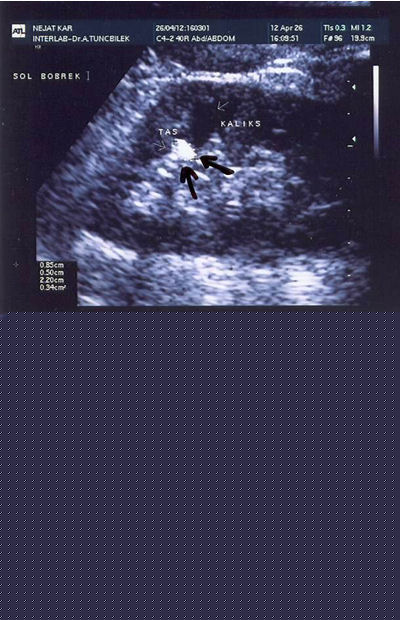

Radiology :

For every patient referred for stone or similar complaints, direct urinary system radiography (DUS) should be taken after the urine test and a complete abdominal ultrasonography (US) should be applied by considering the differential diagnosis.

As we specified above, 85% of the stones include Ca, therefore they may be seen in direct radiographies. US should also be taken to see whether a dilatation is present in the kidney.

If a final diagnosis can not be established by these two tests; Uropgraphy (IVP) taken by administrating colored agents intravenously or Computed Tomography (CT) with or without intravenous colored agent may be utilized.